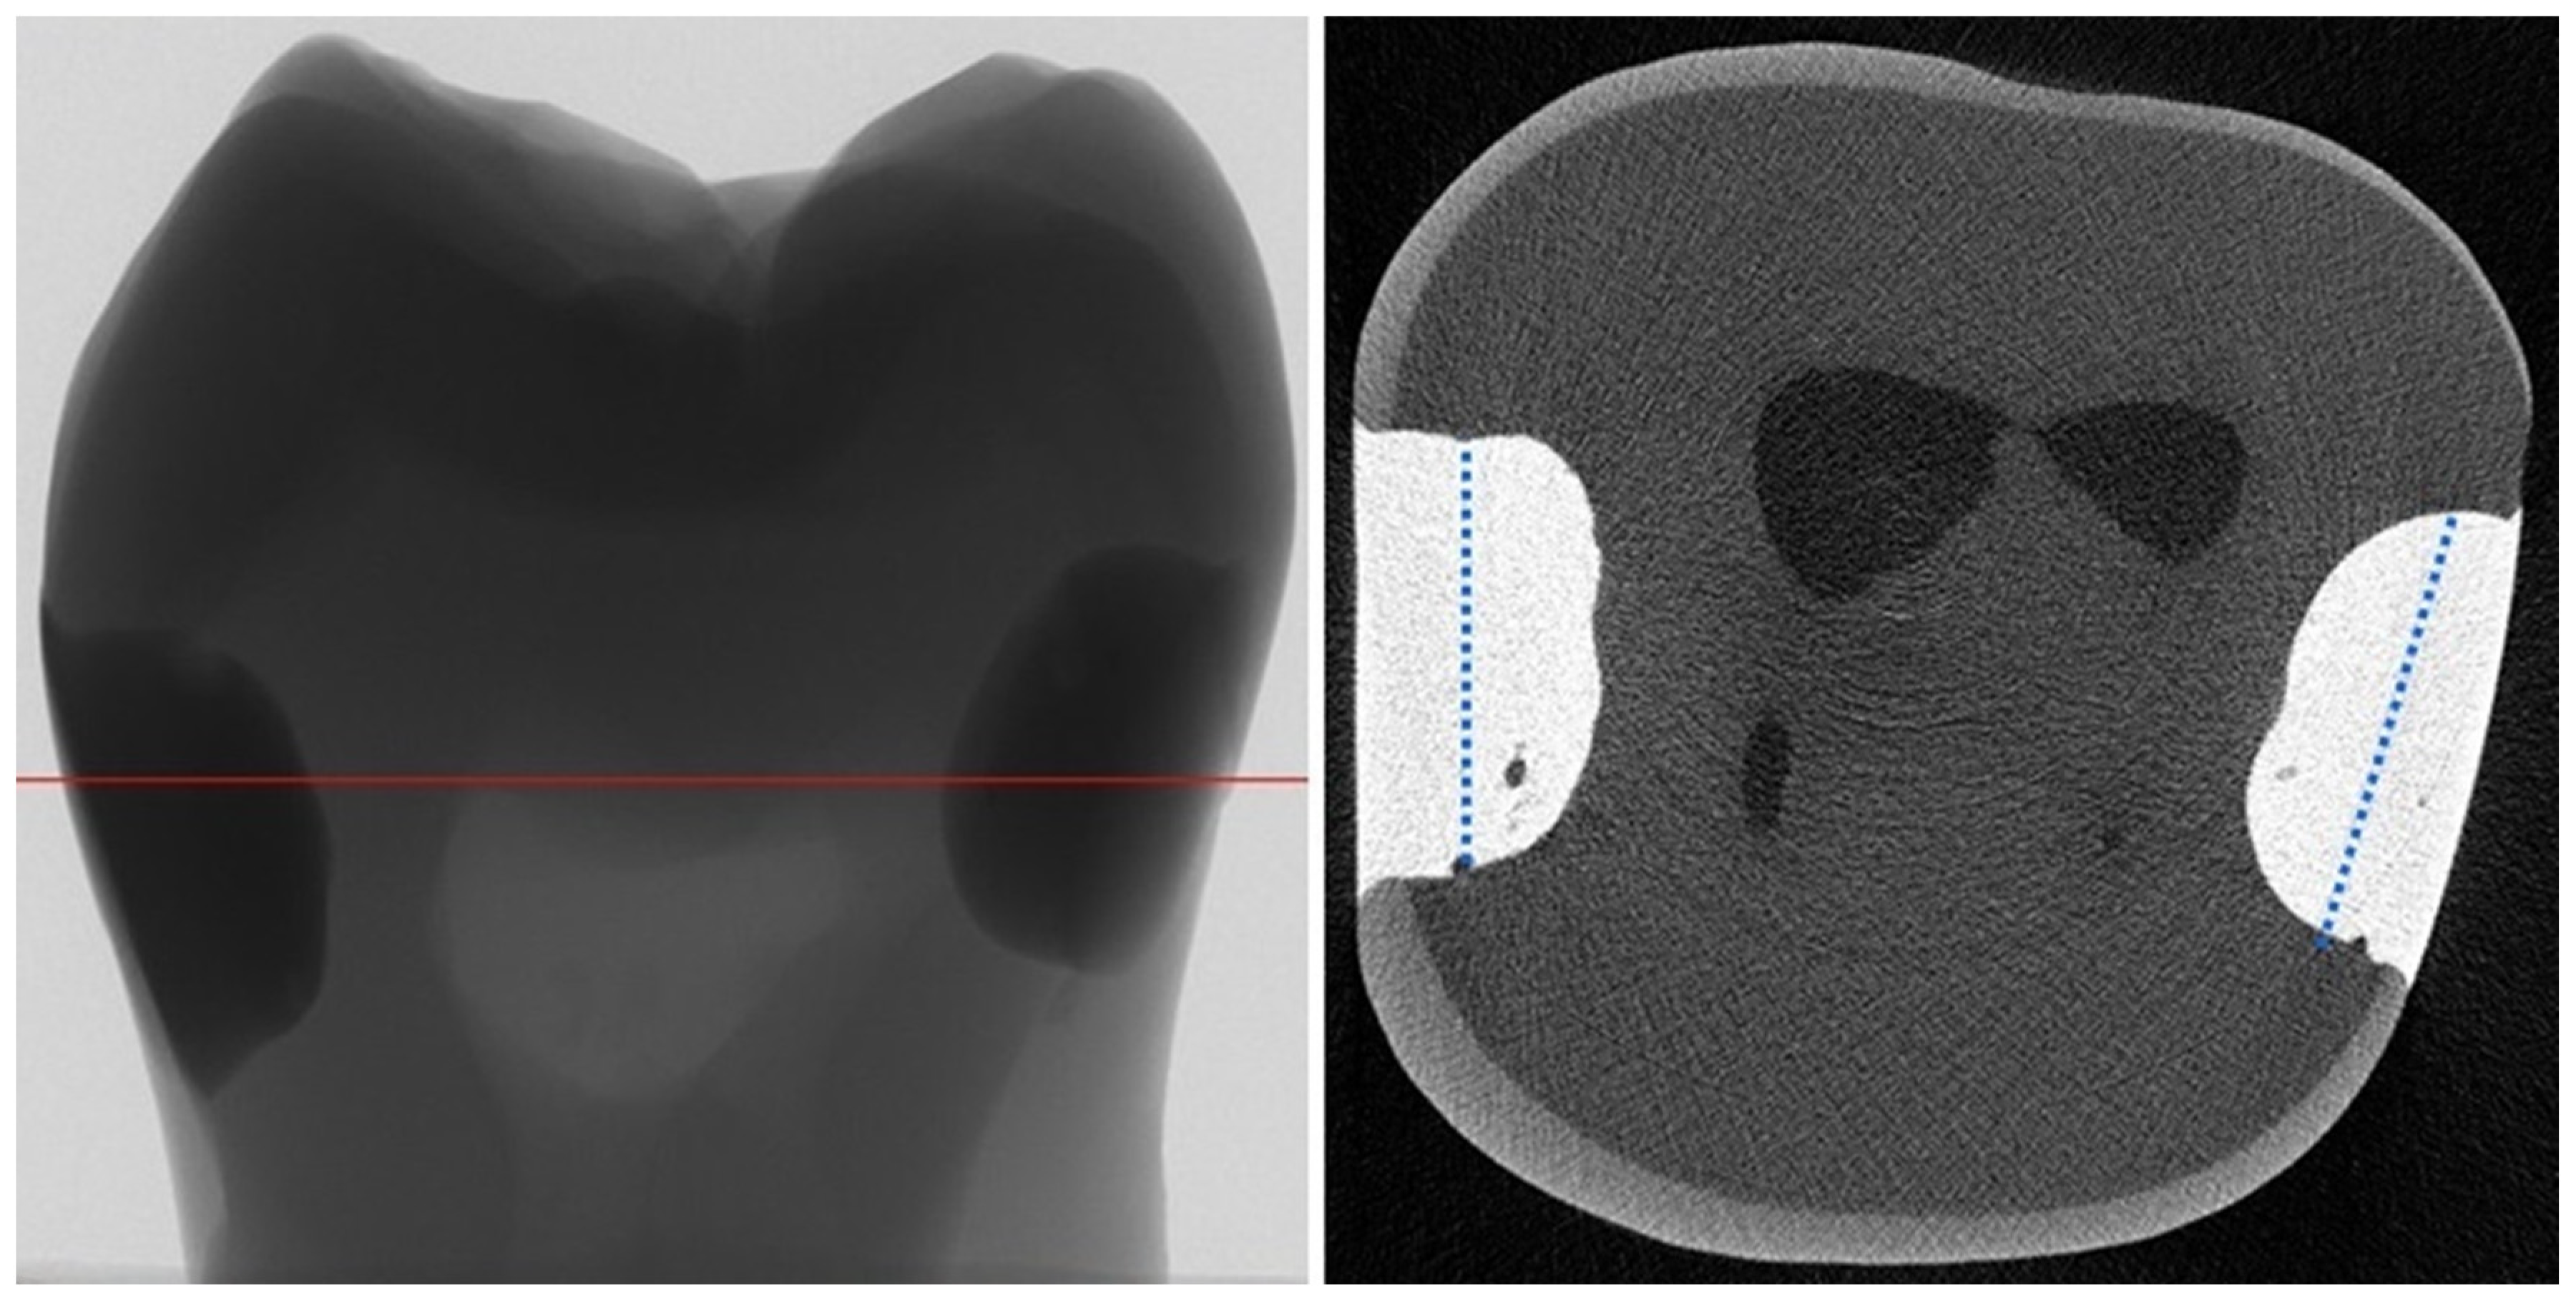

3. Results

4.1. Thermomechanical Loading (TML) and Water Degradation Analysis

4.2. Micro-Computed Tomography (µCT) Analysis

4.3. Gap Volume to Filling Volume (GV/FV) and Gap Volume to Cavity Volume (GV/CV) Ratios

4.4. Gap Volumes at the Tooth–Filling Interface of the External (EGV) and Internal Parts (IGV) of Cavities